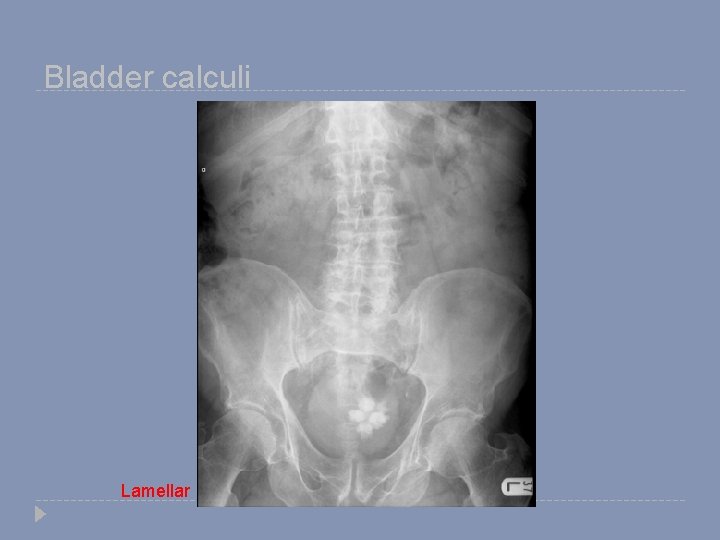

Bladder calculi Lamellar